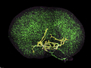

Cells lining the lungs are continuously replaced to fix the damage caused by inhaled particles or pathogens. Replication of basal stem cells (stained green here) provides the source of these replacement cells, but sometimes the process gets out of control – as in the lung cancer specimen shown on the right. Healthy lung tissue, by contrast, is on the left. Studies of lung tissue from healthy people, those with premalignant cancer lesions and those with squamous lung cancer have uncovered a common signalling pathway that's ramped up in patient cells compared with controls. And, researchers have shown that if these signals are experimentally increased in healthy mouse lungs, excessive basal cell proliferation occurs – just like in cancer. Importantly, a recent screen of drug compounds has identified a candidate that can inhibit this signalling pathway in lab-grown human lung cells and prevent their proliferation, offering hope for compound’s clinical development.